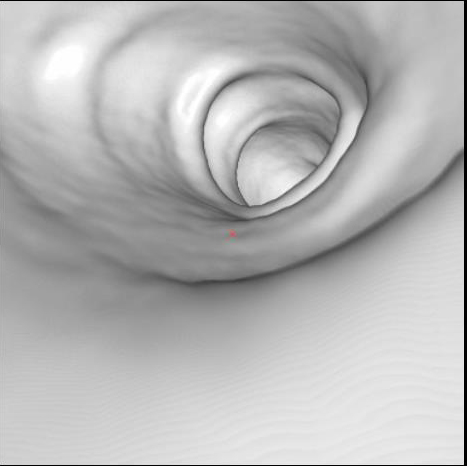

Циркулярный рак тонкой (подвздошной кишки)

Необходимо отметить, что данная патология довольно редко встречается, как правило выявляется на операционном столе у пациентов с тонкокишечной непроходимостью. На данном примере демонстрируем, что дефект кишки был диагностирован на основании 3D реконструкции, а затем уже целенаправленно подтвержден сканограммами с протяженностью процесса и степенью сужения кишечной трубки. Сыграла свою роль сопутствующая патология, которая имела место быть, а именно слабость Баугиниевой заслонки, за счёт чего тонкий кишечник полностью заполнился газом, хотя целью исследования было исключить патологию толстого кишечника.

Просвет тонкой кишки до и после дефекта в 3D-эндоскопе